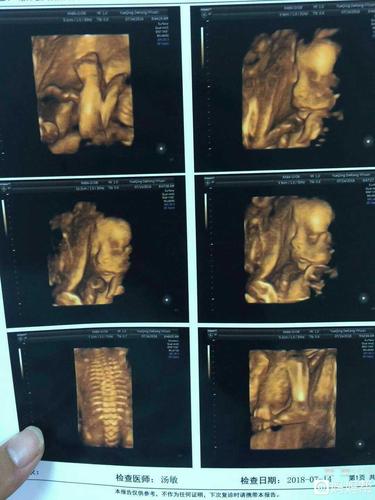

24周四维,24周四维图片胎儿全图

24周四维图片胎儿全图

胎儿24周四维彩超图

四维彩超

20周胎儿四维真实图片

四维图片胎儿全图